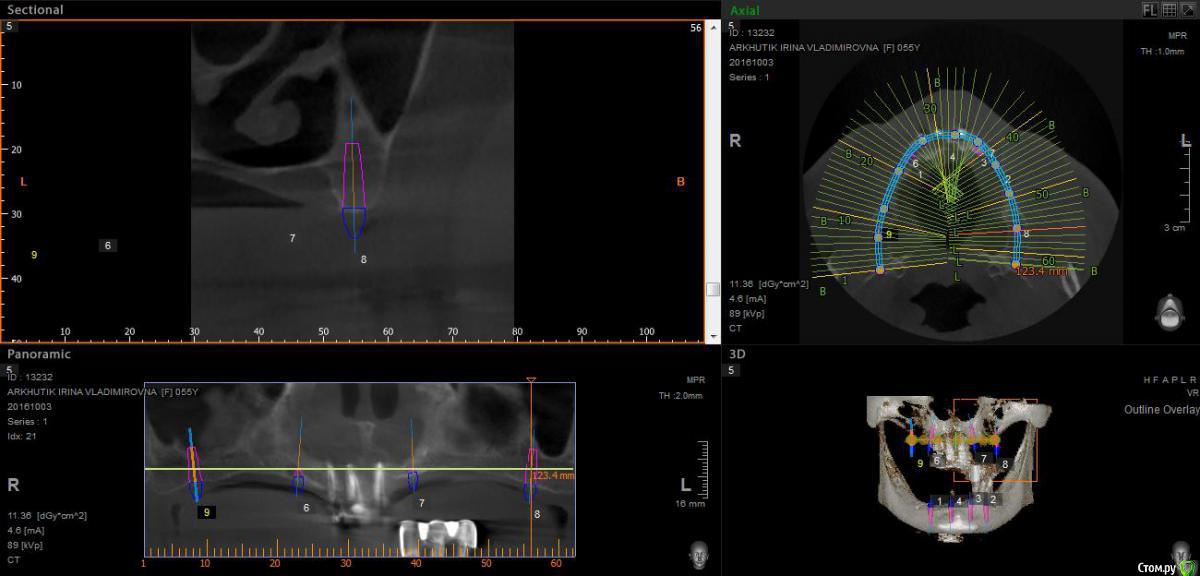

Rusty Опубликовано 5 октября, 2016 Поделиться Опубликовано 5 октября, 2016 Добрый день. К ортопеду обратилась пациентка 55-60 лет с такой ситуацией. Пришла с дочкой, дочь с мамой настаивали на несьемной конструкции, ортопед отправил на кт и вот. Не хочу планировать ей много хирургии, оцените и мой план пожалуйста и буду рад услышать советы по реабилитации пациента. По сути да) просто искал место куда есть возможность поставить, ортопед говорит тогда балка либо локаторы Ссылка на комментарий

Nazim_NV86 Опубликовано 5 октября, 2016 Поделиться Опубликовано 5 октября, 2016 На н/ч балка? Какие измерения в дист отделах? На в/ч мало четырёх. По три бы. Ссылка на комментарий

Rusty Опубликовано 5 октября, 2016 Автор Поделиться Опубликовано 5 октября, 2016 На н/ч балка? Какие измерения в дист отделах? На в/ч мало четырёх. По три бы.На н/ч балка, в дистальных отделах над каналом около 3мм. На вч условий для установки больше 4 не нашел) Ссылка на комментарий